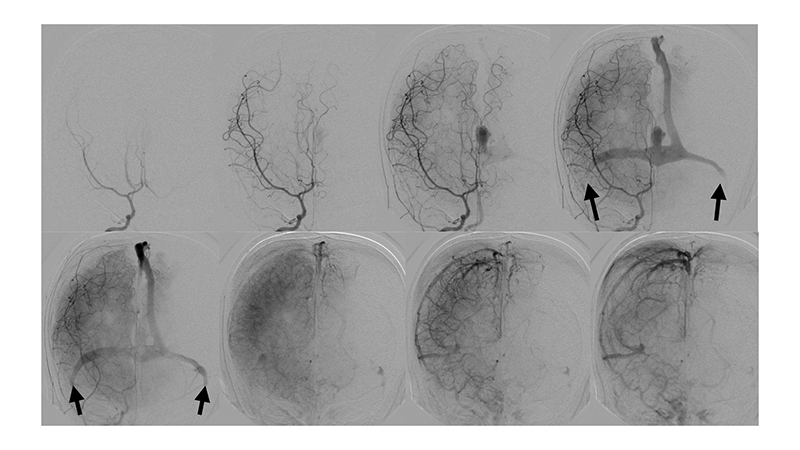

- Προσθιοπίσθια λήψη κατά την έγχυση στην δεξιά έσω καρωτίδα. Η αρτηριοφλεβώδης επικοινωνία της φλέβας του Γαληνού σκιαγραφείται από παλινδρόμηση στην δεξιά υποκλείδιο και σπονδυλική αρτηρία. Η φλεβική παροχέτευση του δεξιού εγκεφαλικού ημισφαιρίου γίνεται πολύ καθυστερημένα, λόγω απόφραξης των εγκαρσίων κόλπων αμφοτερόπλευρα (μαύρα βέλη).

- Προσθιοπίσθια λήψη κατά την έγχυση στην αριστερή έσω καρωτίδα. Η αρτηριοφλεβώδης επικοινωνία της φλέβας του Γαληνού σκιαγραφείται από την οπίσθια αναστομωτική αρτηρία. Η φλεβική παροχέτευση του αριστερού εγκεφαλικού ημισφαιρίου γίνεται πολύ καθυστερημένα, λόγω απόφραξης των εγκαρσίων κόλπων αμφοτερόπλευρα (μαύρα βέλη).